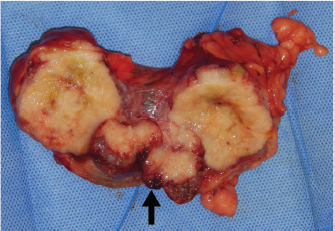

The main finding at necropsy was two poorly delimited, firm white multinodular masses in the urinary bladder, the first 8 × 4 × 3cm3 dorsally and the second roughly 3 cm in diameter towards the neck (Fig. 2). The bladder mucosa had multiple petechiae.

Fig. 2. Urinary bladder lumen of a maned wolf with multiple firm tumor nodules coalescing around the bladder neck (arrow).